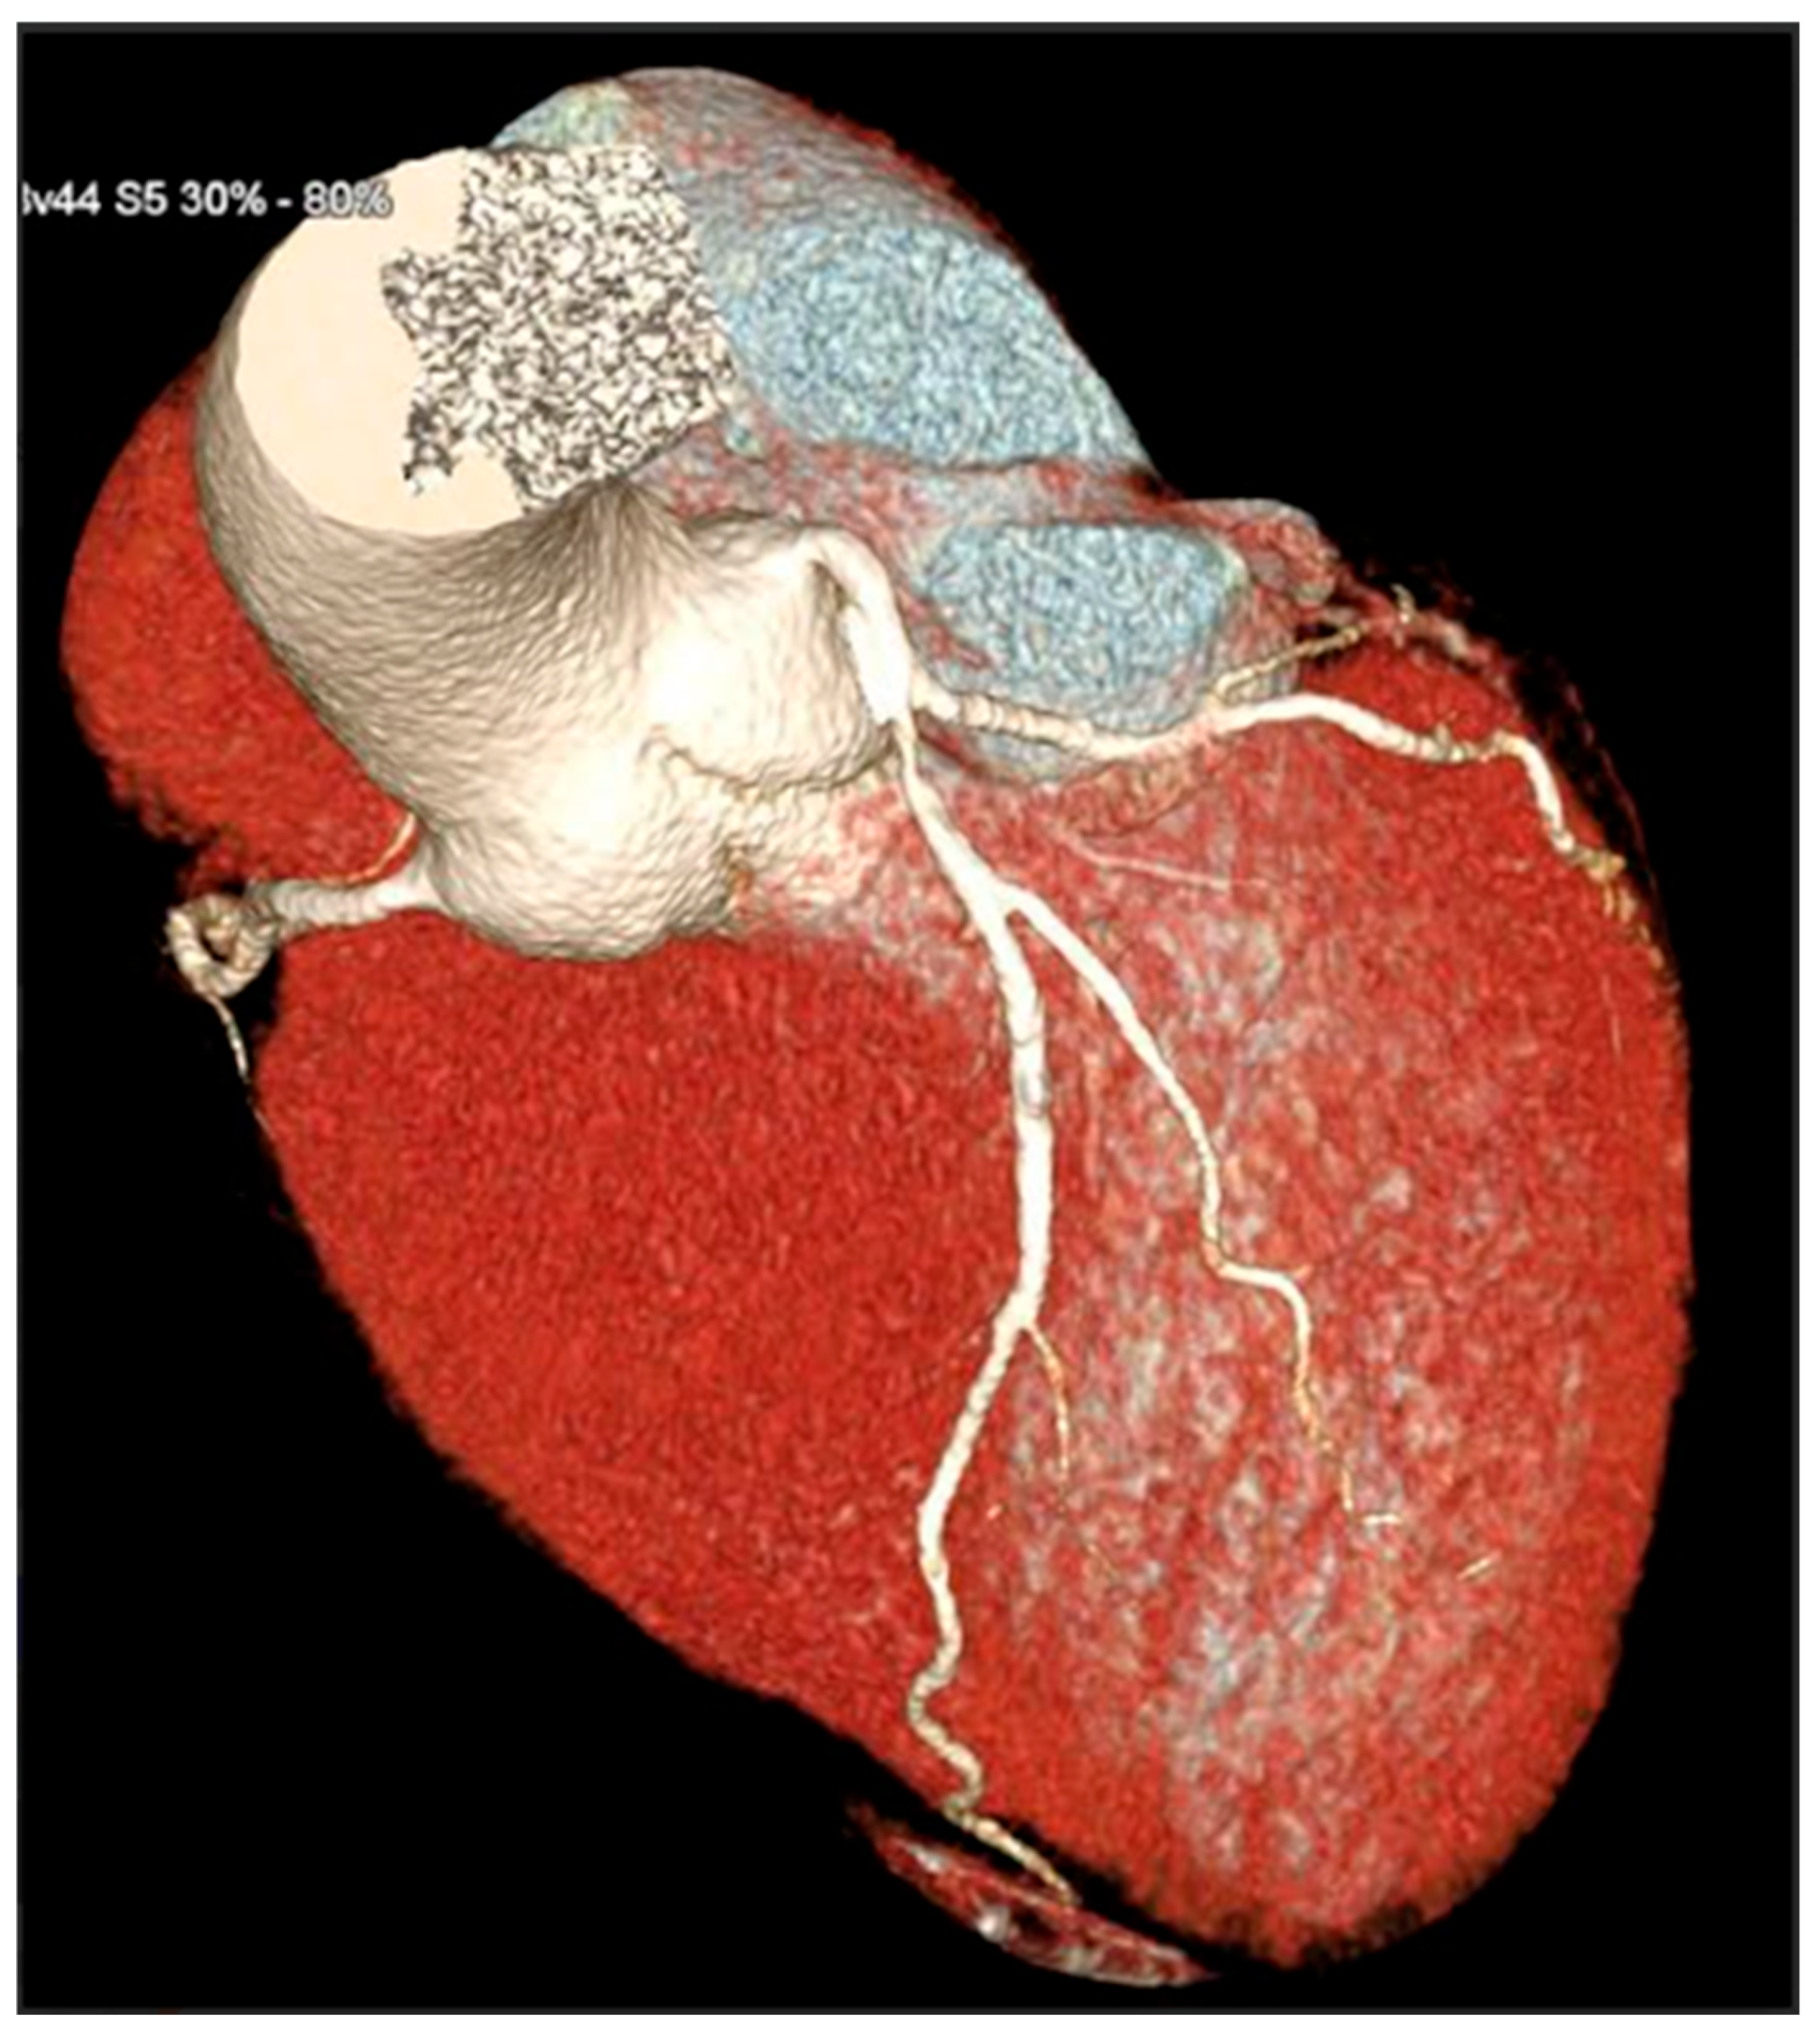

CCTA scans were acquired using a 128-slice single-tube Siemens CT scanner (Definition AS+, Siemens Healthcare, Forchheim, Germany) in a retrospectively ECG-gated sequential mode. Acquisition parameters included collimation of 128 × 0.6 mm, gantry rotation time of 0.3 s, and application of automatic tube current modulation (CARE Dose 4D) with voltage settings adapted to body habitus (typically 100–120 kV). The scanning range extended from the carina to the diaphragm, with ECG triggering centered at 70% of the R-R interval. Patient preparation included oral administration of a beta-blocker (e.g., atenolol) one day before the scan to target a heart rate < 65 bpm. On the day of the scan, sublingual nitroglycerin (0.4–0.8 mg) was administered 5 min prior to acquisition to achieve coronary vasodilation. Contrast injection consisted of 70–75 mL of Iopamidol (370 mgI/mL) followed by 40 mL of saline flush, injected at 5.5 mL/s via an antecubital vein. Bolus tracking was performed at the level of the ascending aorta, with a threshold of 150 Hounsfield Units to initiate the scan. Image reconstruction employed a slice thickness of 0.6 mm with 0.4 mm increment and iterative reconstruction algorithms (SAFIRE or ADMIRE), using a dedicated coronary kernel (e.g., B26f or B40f BV 44f). If necessary, motion correction was performed using multi-segment reconstruction. Post-processing included multiplanar reconstructions (MPRs), curved planar reconstructions (CPRs), maximum intensity projections (MIPs), and 3D volume rendering (VR), conducted on Syngo.via workstations. Coronary artery analysis followed the American Heart Association 16-segment model. Coronary stenosis was classified as significant when luminal narrowing exceeded 50% or 70%, based on consensus by at least two out of three experienced CCTA readers. CCTA examinations were interpreted by experienced cardiovascular imaging readers with >5 years of dedicated CCTA experience and annual volumes exceeding 300 studies per reader. Coronary stenosis severity and plaque morphology were assessed by consensus of at least two readers; in case of disagreement, a third senior reader adjudicated. Readers had access to standard clinical referral information but were blinded to carotid duplex ultrasound findings and CAC score at the time of plaque morphology assessment. A 3D reconstruction allowed for a comprehensive reconstruction of the anatomy of coronary arteries (Figure 3).

Figure 3.

3D reconstruction of coronary CT angiography showing a significant stenosis in the proximal segment of the left anterior descending coronary artery.